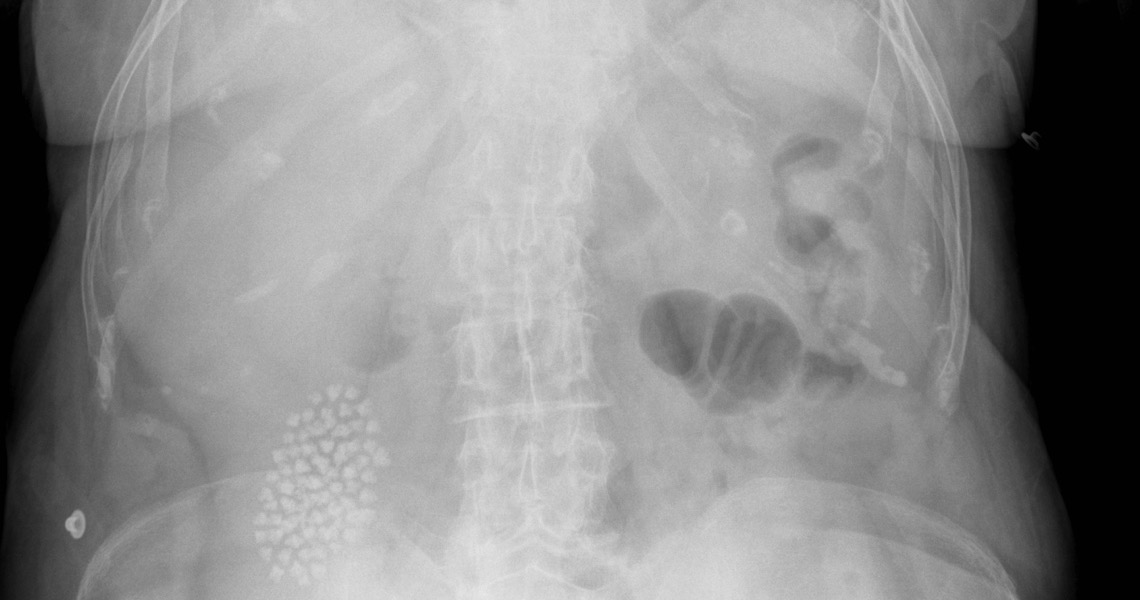

Gallstones can be discovered accidentally during an abdominal ultrasound due to an unrelated problem or illness.